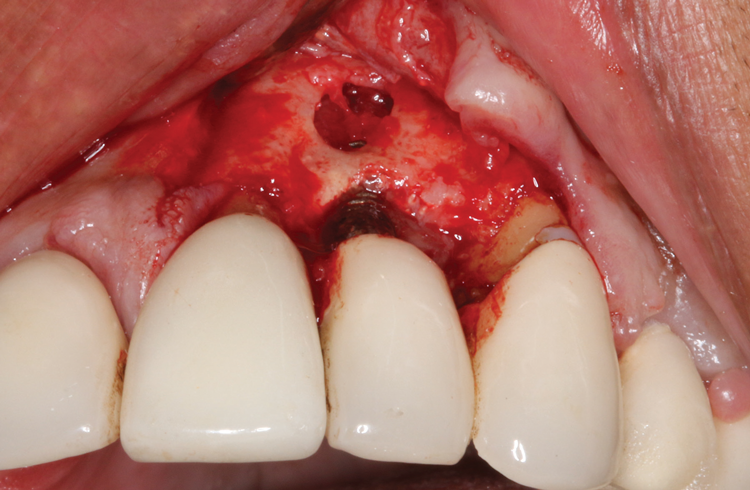

This is where the treatment became challenging. First, a curette was used to attempt to remove the granulation tissue from around the apex of the implant circumferentially. This was a difficult endeavor, especially on the palatal aspect of the site. Following curettage, an 810 nm diode laser (NV® PRO3, DenMat [alternatively: Picasso+, AMD Lasers; Gemini, Ultradent]) was used to treat the apical portion of the implant. After the laser tip was initiated using dark occlusal paper (Figure 4), it was used to debride the remaining necrotic tissue and decontaminate the entire site, reducing the bacterial count (Figure 5 and Figure 6).

(5.) The physical granulation tissue was ablated, and the entire site was decontaminated, reducing the bacterial count.

Figure 5

(6.) View of the cleaned site ready to be repaired.

Figure 6